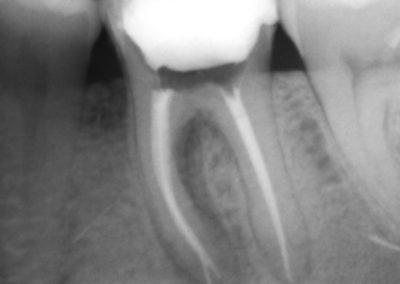

An access cavity is placed on the surface where the patient bites, to reach the root canals of the tooth. Once all the canals are identified, small files are used to remove the infected pulp.

Files of different sizes are used to eliminate bacteria and infection and to shape the canals. The canals are disinfected thoroughly with irrigants and later the canals will be sealed in 3 dimensions with a special medicament called gutta-percha to prevent reinfection of the tooth and the access cavity will be sealed with a temporary filling.